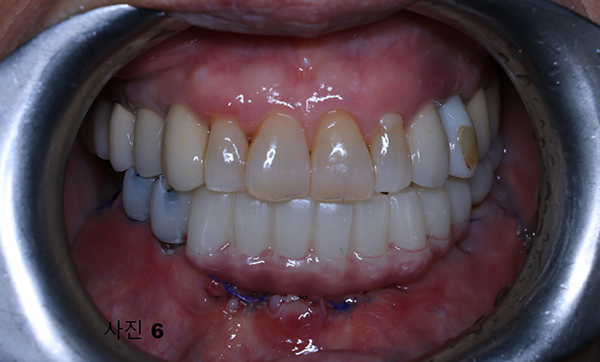

(사진5)과 같이 5개의 임플란트를 식립해 4개를 사용하여, (사진6)과 같이 본원에서 CAD/CAM을 이용하여 풀아치 임시 보철물을 제작하여

심미적,기능적인 면을 수술후 빠른 시간내에 환자분이 만족스럽게 임시치아를 만들어 주었다.